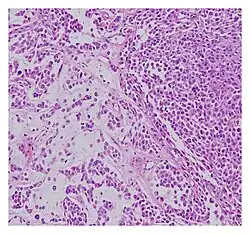

| Histopathological examination of malignant chondroid syringoma | |

Histologically, these malignant mixed tumours have epithelial and mesenchymal components and are very large, nodular, circumscribed, and nonulcerated.[11] They are morphologically identical to pleomorphic adenoma and have a female predilection.[4] They range from developing deep dermal to subcutaneous nodules and metastasise at a very high rate.[4][8] Malignant mixed tumours can emerge "de nova or more rarely develop from a cartilaginous syringoma."(IADVL, 2004)[11]

Diagnosing malignant mixed tumours is difficult as there many types of tumours and their variants.[9] Malignant chondroid syringoma is particularly challenging to distinguish from other skin tumours as it is prone to the absence of definitive symptoms and an ambiguous clinical presentation.[3] Some signs that help determine diagnosis of malignancy include: "mitosis, nuclear atypia, pleomorphism, lymphatic invasion, and local recurrence" (IADVL, 2004).[11] Though it is usually found within women in the forties, the youngest-recorded case was fourteen years old and the oldest was eighty-six.[12] The tumour is described as invasive[12] and is clinically characterised by faster growth than the benign chondroid syringoma. They can generally be diagnosed when presenting "an epithelial component, eccrine or apocrine differentiation and myoepithelial component of fluctuating prominence" (IADVL, 2004).[11] Diagnosis is recommended to follow microscopic analysis to ensure correct examination.[8]

“small groups as well as scattered pleomorphic epithelial cells having hyperchromatic nuclei and scanty cytoplasm with one to two mitotic figures of high power field, surrounded by abundant basophilic chondromyxoid stroma, diagnostic of malignant CS.”[2]

“ten centimetre, firm, lobulated mass with skin ulceration and muscle involvement was removed. Microscopic examination revealed infiltrating nests of medium to large epithelial cells embedded in a chondromyxoid matrix with few scattered plasmacytoid myoepithelial cells. There was brisk mitosis as well as large areas of tumour necrosis. All auxiliary lymph nodes were negative for tumour.”[3] (Garcia, Atun, and Fernando, 2016)

“The surgical specimen showed a lobular proliferation of tumour cells with glandular differentiation associated with a few mitotic cells, embedded in a mucinous stroma. Immunohistochemistry showed that the majority of tumour cells were positive for PAS diastase, toluidine blue, cytokeratins (CAM5.2, CK7), S-100 protein and GCDFP-15.”[10]